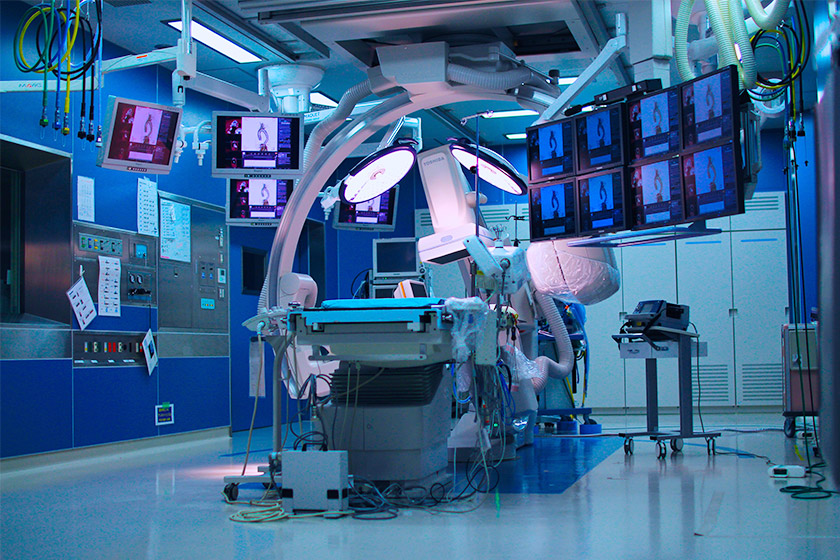

留置手技

WATCHMANの留置は

どのように実施されるのでしょうか

非弁膜症性心房細動の患者さんでは、脳卒中の原因となる血栓の90%以上が左心房に起始する左心耳(LAA:Left Atrial Appendage)で形成されたものです。

WATCHMANはこのLAAを閉鎖して血栓の形成を防ぎます。手技は経静脈的心房中隔穿刺法であり、カテーテル室において全身麻酔下で実施します。

通常、手技は約1時間を要し、手技の数日後に退院できます。手技後、約45日または十分な閉鎖が得られるまで、アスピリンおよび抗凝固剤を投与します。抗凝固剤投与中止後、チエノピリジン系薬剤とアスピリンを約6ヵ月間投与し、その後はアスピリン単剤投与を継続します。

手技手順

1

1

経皮的アプローチでガイドワイヤとダイレーターを右大腿静脈に挿入します。

2

2

X線と経食道心エコー(TEE)下で留置手技を実施します。経心房中隔穿刺システムを用いて心房中隔を通過します。

3

3

ガイドワイヤに沿って、アクセスシースを左上肺静脈または左心房内に進めます。次に、ピッグテールカテーテルに沿ってLAAの遠位側に誘導します。

4

4

WATCHMANを展開し、LAAに留置します。

5

5

WATCHMANを覆うように内皮化が進み、LAAが永久的に閉鎖されます。患者さんは、手技後約45日間は抗凝固薬の内服を継続します。経食道心エコーで閉鎖していることを確認します。